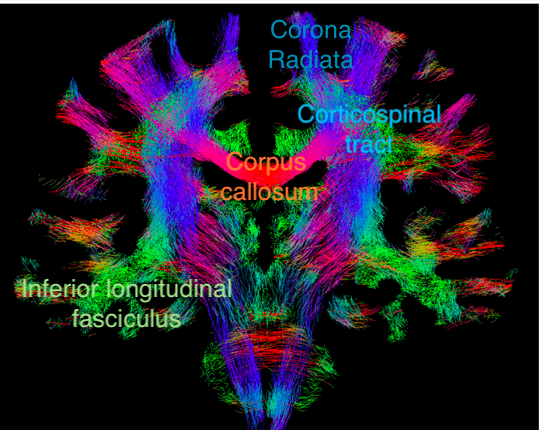

Major white matter tracts in the brain can be visualised by tractography (DTI) and can be useful in neurosurgical planning. The directions of the tracts are colour-coded: craniocaudal in blue (my mnemonic: to the sky), left-right in red (you cannot go ahead at a red light) and anterior-posterior in green (you can go ahead at a green light).

Figure 2. Coronal section showing fiber-tracking results.

Adjusted from an article by F. Calamante elucidating the pitfalls of DTI. https://doi.org/10.3390/diagnostics9030115